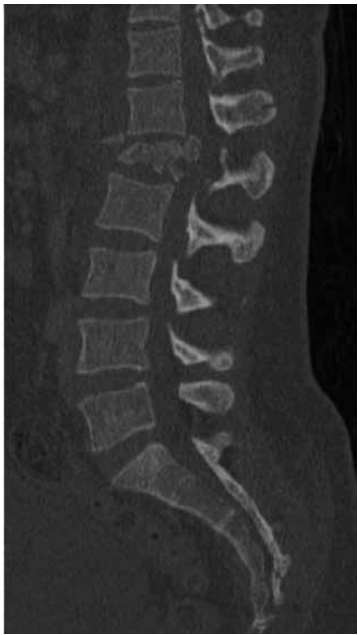

Paciente de 87 anos de idade relata dor na região lombar, em queimação, que irradia para membro inferior direito, associada a formigamento. A dor surgiu de forma súbita após o paciente desequilibrar-se e sofrer uma queda com impacto na região glútea. Desde então, a dor vem de forma contínua, sem fatores de melhora ou piora. Foi realizada uma ressonância magnética da coluna:

(Arquivo pessoal; imagem usada com autorização)

Diante dessa condição clínica, assinale a alternativa correta quanto à conduta a ser tomada.